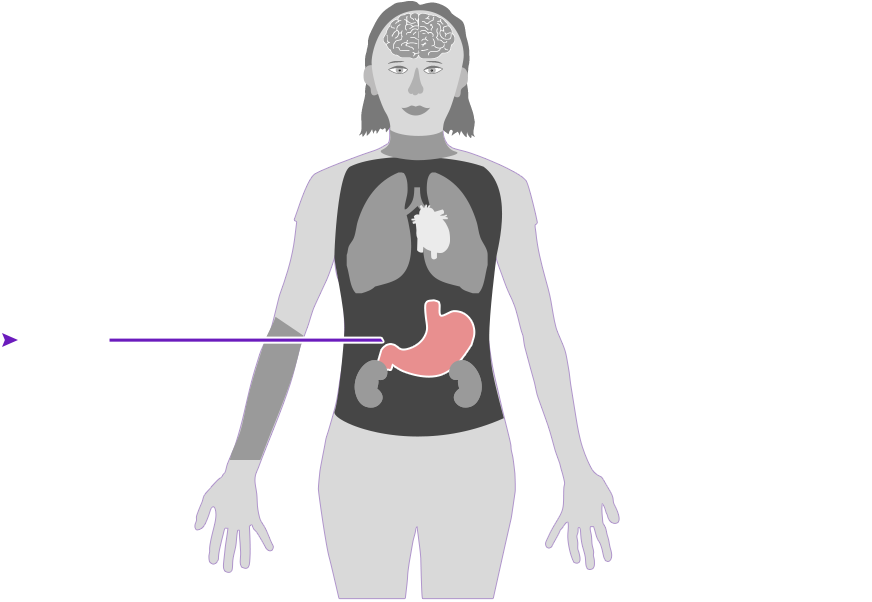

Check out how mercury can affect the human body. Click on the different parts of the body to see what can happen when people are poisoned by mercury. How serious these health effects are may vary depending on how much mercury gets into your body — and how long you breathe it in.

Health effect caused by breathing in high levels of mercury vapors (fumes) over a short period of time

Health effect caused by breathing in high levels of mercury vapors (fumes) over a short period of time  Health effect caused by breathing in lower levels of mercury vapors over a long period of time

Health effect caused by breathing in lower levels of mercury vapors over a long period of time